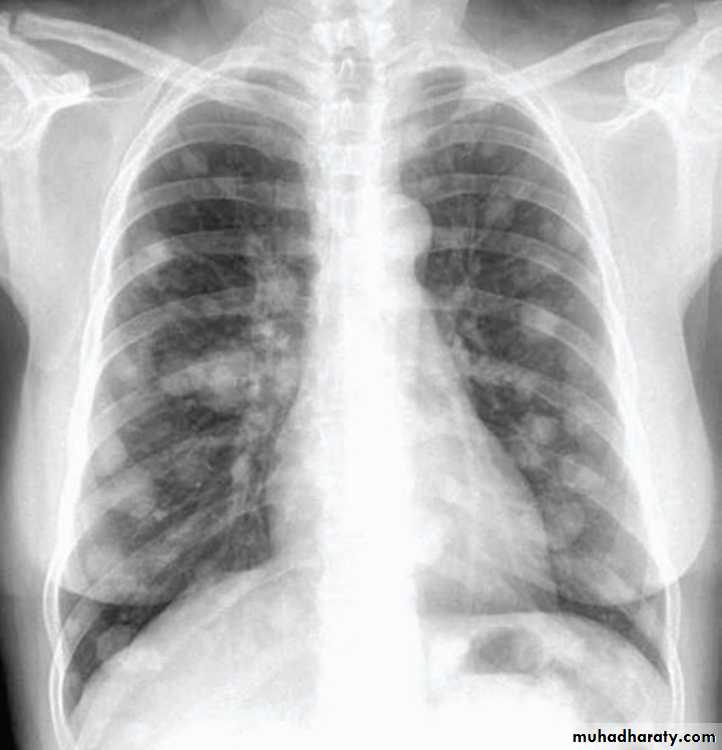

A non smoker 45 years-old women with history of ovarian tumor presented with mild dyspnea.• OE: Non-specific lung findings.

• CXR shows multiple nodules of different size.

What’s your primary impression?

Metastases in the lung are very common and usually present as round shadows (1.5-3.0 cm diameter). They may be detected on chest X-ray in patients already diagnosed as having carcinoma.Typical sites for the primary tumor include the kidney, prostate, breast, bone, gastrointestinal tract, cervix and ovary.

Metastases nearly always develop in the parenchyma and are often relatively asymptomatic even when the chest X-ray shows extensive pulmonary metastases

( cannon ball metastasis)